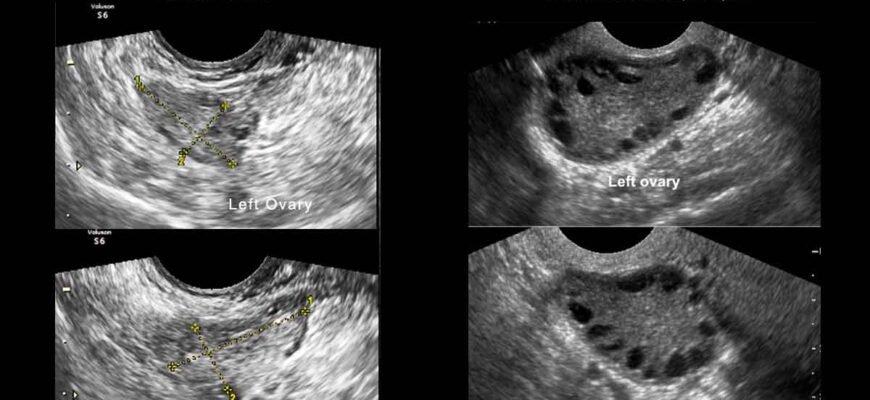

Діагностика — не з легких. Вона вимагає ультразвукового дослідження, аналізу гормонів та інших обстежень. Іноді процес нагадує детективний фільм, де треба зібрати всі шматочки пазлу, щоб дійти до висновку. Надійний гінеколог — ваш кращий друг у цій ситуації.